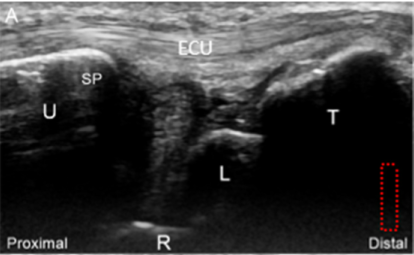

민트색 박스 표시한

척골 경상돌기(Sp)에 프로브를 대고

TFCC 장축 스캔을 하면요.

가장 바깥에

척측수근신근 힘줄이 보이고요.**

(ECU, extensor carpi ulnaris)

잘 보이시진 않겠지만

힘줄집(subsheath)을

신전근 지대(Extensor retinaculum)가

감싸고 있는 형태입니다.

그 아래에 파란색으로 표시한

척골 측부인대(Ulnar collateral ligament)

가 보입니다.

그 아래는 빨간색으로 표시한

반월 연골 유사체(Meniscus homologue)

가 보이고요.

그 아래는 귤색으로 표시한

요척 인대(Radio-Ulnar ligament)

얕은층(superior limb)와

깊은층(deep limb)으로 보입니다.